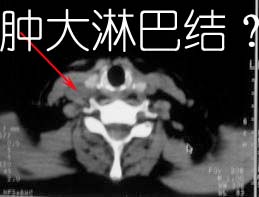

考虑淋巴结炎[两个];左上颌窦炎性积液

支持,考虑2处均为淋巴结炎。

至于右侧颌下间隙的结节影,如果不考虑病史的话,可以诊断为淋巴结转移。但是结合病史“右侧颌下肿物3年”,又不象淋巴结转移了。建议ct增强扫描明确结节与右侧颌下腺的关系,或者穿刺活检定性。